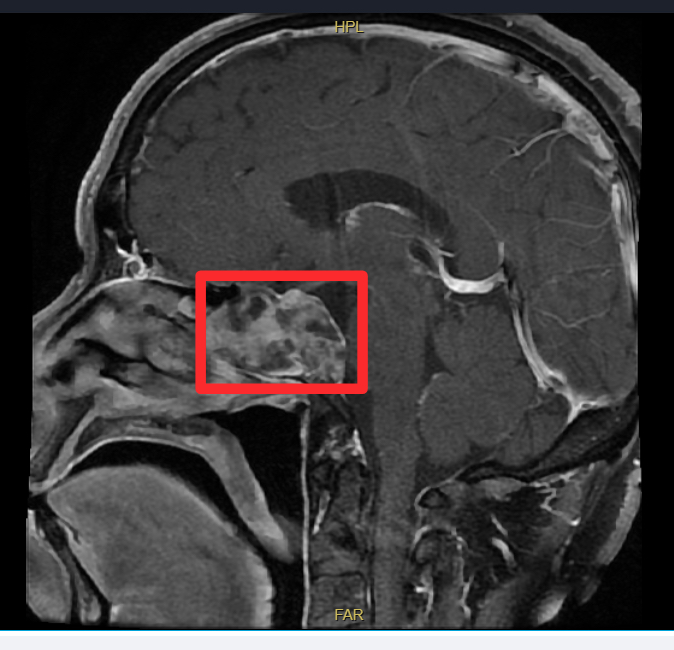

影像学提示鼻腔深部存在肿物

数月前,年过六旬的陈先生(化名)开始出现左侧鼻腔流脓涕、头晕并伴有反复鼻出血。起初他并未在意,但在当地医院检查后,结果却让人心头一紧——影像学提示其鼻腔深部存在肿物。由于病灶位置深,紧邻重要神经血管且毗邻颅脑,手术风险极高,当地医院建议他立即转往上级医院。

怀着一线希望,陈先生来到了中大医院,找到了擅长鼻及鼻颅底手术的孙宝宾副主任医师。经过详细的术前检查和评估,孙宝宾副主任医师团队认为肿瘤很可能起源于颅底的蝶窦区域,并已对周围骨质造成了侵蚀。为明确肿瘤性质,团队为其实施鼻内镜下蝶窦肿物活检术。术后病理报告确诊为脊索瘤。